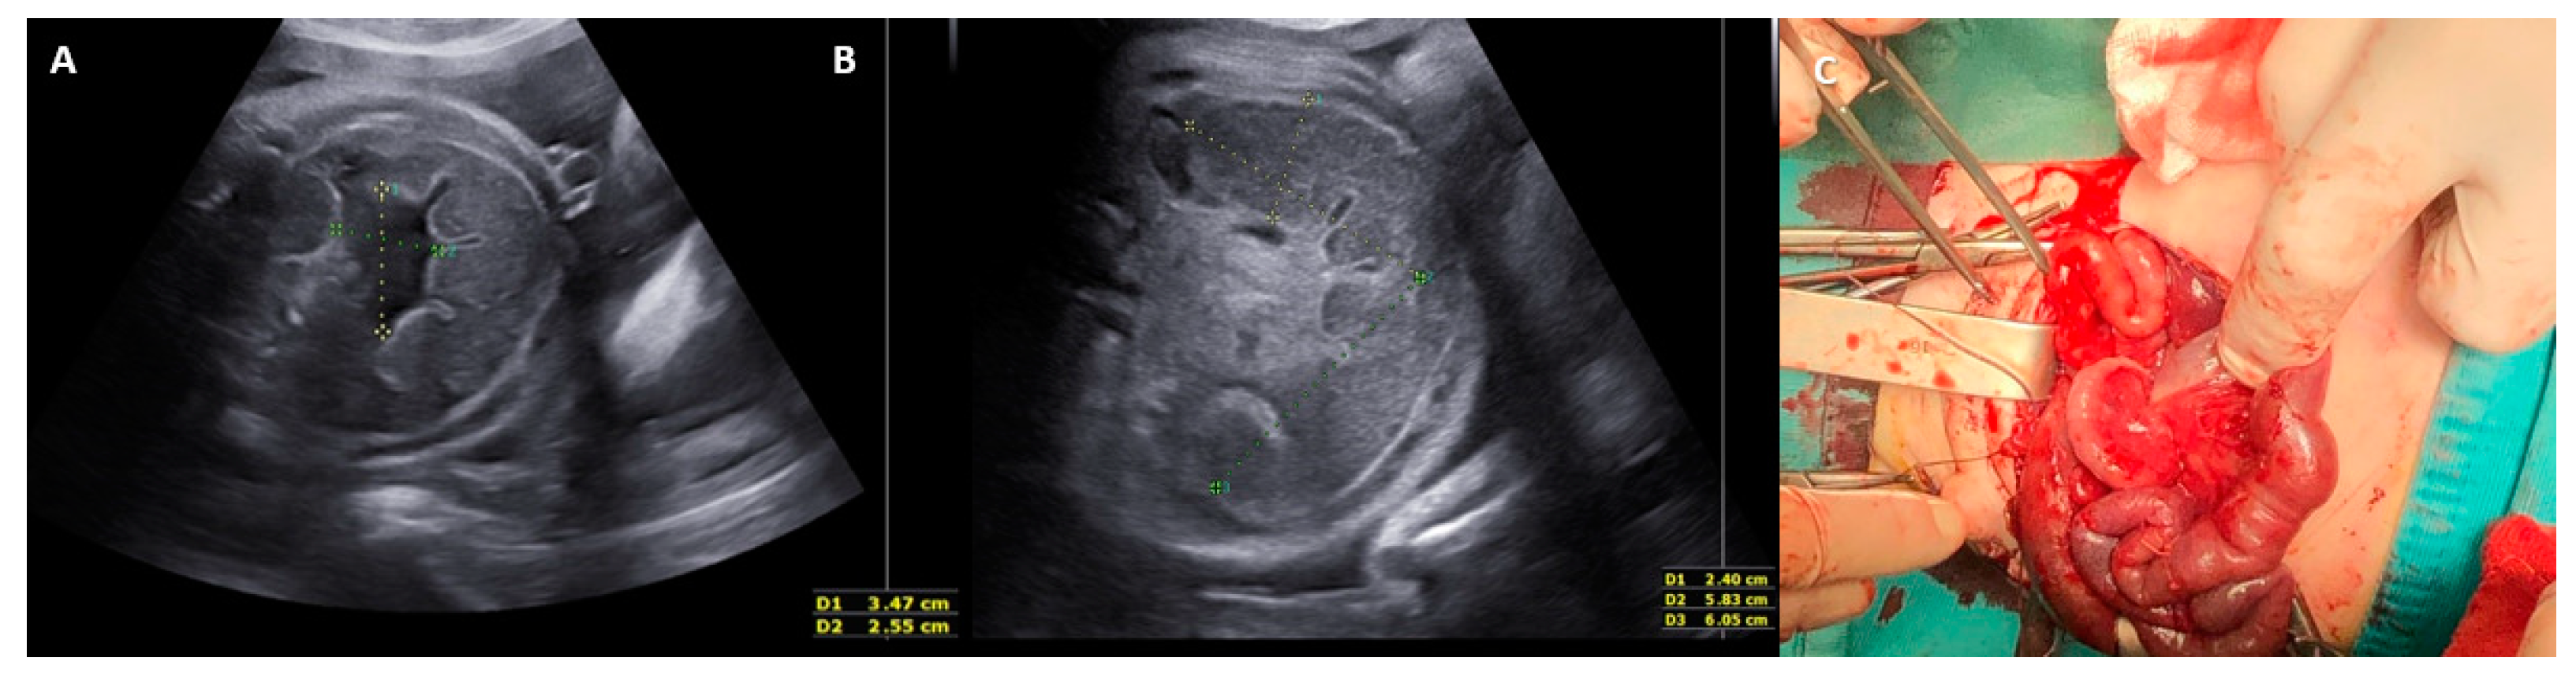

- One case of idiopathic midgut volvulus born after a cesarean section performed at 35 GW for non-reassuring FHR, despite the fetus showing severe signs suggestive of intestinal volvulus on US (whirlpool sign, fluid-meconium levels, bowel dilatation, meconium peritonitis) and signs of fetal distress (↓ FMs) after 34 GW.

- One case of midgut volvulus with necrosis and perforation, intestinal atresia, and duplication. The baby died on day 36 of intraventricular hemorrhage and sepsis. The baby was born at 35 GW after a spontaneous vaginal delivery. A US follow-up was carried out from GW 34 despite the fetus showing signs of distress (preterm labor) and worsening of US findings of the volvulus, such as severe hydramnios, whirlpool sign (with no flow signal and subsequent disappearance), ↑ bowel dilatation, and thick ascites of mixed echogenicity.